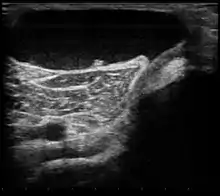

Ultrasound image of Baker's cyst

Diagnosis is by examination. A Baker's cyst is easier to see from behind with the patient standing with knees fully extended. It is most easily palpated (felt) with the knee partially flexed. Diagnosis is confirmed by ultrasonography, although if needed and there is no suspicion of a popliteal artery aneurysm then aspiration of synovial fluid from the cyst may be undertaken with care. An MRI image can reveal presence of a Baker's cyst.